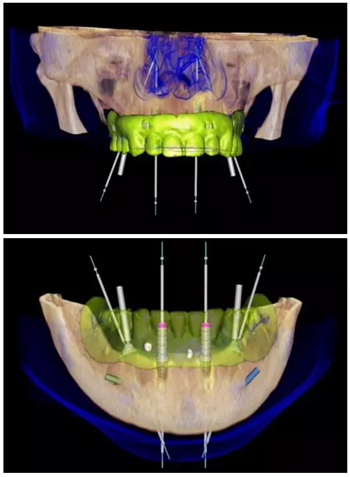

數(shù)字化治療方案設(shè)計(jì)

使用NobelClinician針對上頜及下頜分別進(jìn)行數(shù)字化的種植修復(fù)方案設(shè)計(jì)。